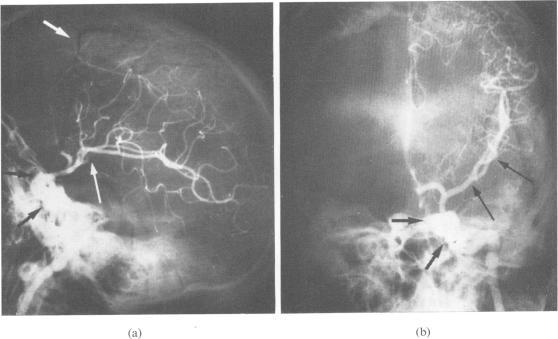

Surgical management of an unusual carotid-cavernous fistula.

Carotid-cavernous fistula: a complication of maxillofacial trauma.

Traumatic carotido--cavernous fistulas.

Bilateral carotid-cavernous fistulae: a review.

Carotid cavernous fistula.

THE TREATMENT OF CAROTID CAVERNOUS ARTERIOVENOUS ANEURYSMS.

Artificial embolization of carotid-cavernous fistula with post-operative patency of internal carotid artery.